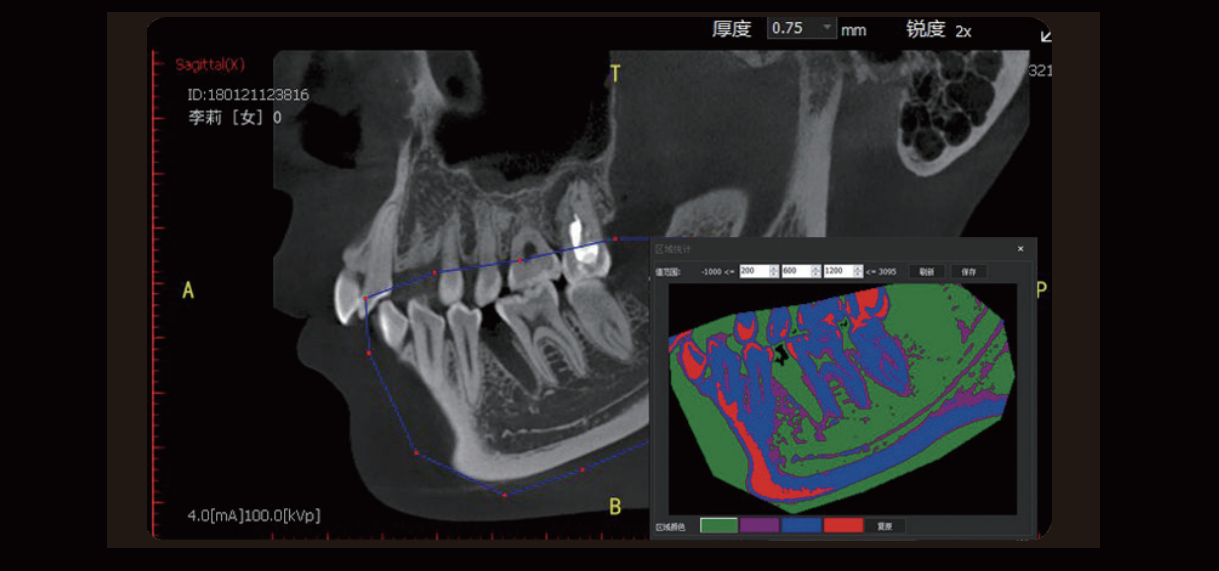

Density Measurement

Visual assessment of bone quality, bringing greater convenience to dentists.